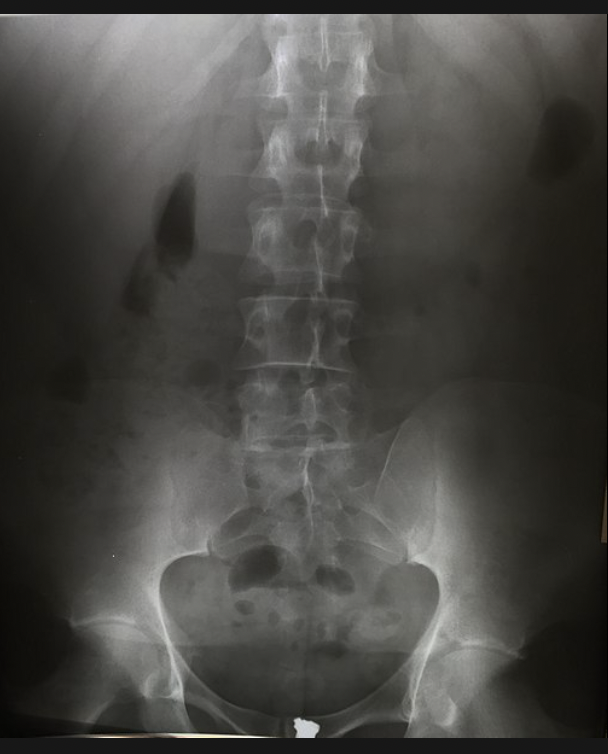

Ankylosing spondylitis

normal spine